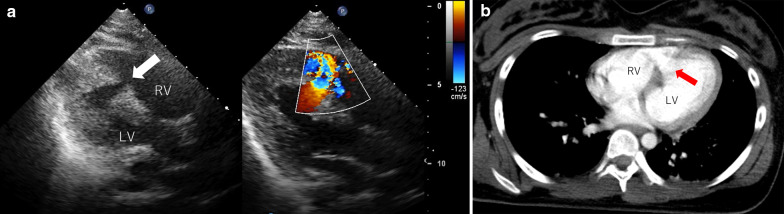

Cardiac injury, including myocardial contusion and valvular damage, is a common complication of blunt chest trauma; however, traumatic ventricular septal rupture is a rare complication. We encountered a rare case of ventricular septal rupture following blunt chest trauma that was successfully repaired by emergency surgery. The mechanism underlying rupture may involve acute compression of the heart between the sternum and the vertebral column when the ventricle is filled, thereby causing a sudden increase in intraventricular pressure and leading to septal rupture. Emergency operation should be considered in cases of large defects and hemodynamic instability.